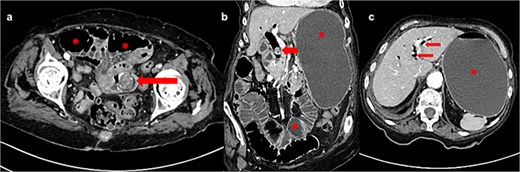

An 88-year-old lady was admitted to our institution due to vomiting for 4 days and hematemesis on admission. The patient was icteric, hypotensive, with a distended abdominal wall and periumbilical pain on palpation. Her past medical history included permanent atrial fibrillation on warfarin, hypothyroidism, and chronic kidney disease. Laboratory testing revealed leukocytosis (leucocytes 13.3 × 109/L), normal hematocrit (0.36 L/L), elevated C-reactive protein level (CRP 89 mg/L), INR >6.0, glomerular filtration rate of 25 ml/min/1.73 m2, elevated bilirubin level (total bilirubin 57 μmol/L; reference range 3–20) as well as elevated hepatic aminotransferases [alanine aminotransferase 76 U/L (reference range 10–36), aspartate aminotransferase 113 U/L (reference range 8–30), gamma glutamyl transferase 54 U/L (reference range 9–35), alkaline phosphatase 87 U/L (reference range 64–153)]. Abdominal computed tomography (CT) scan showed intestinal obstruction in the jejunum caused by a gallstone, a gallstone in the dilated bile duct, stomach/jejunal dilatation and hepatic pneumobilia (Fig. 1). The patient received prothrombin complex concentrate, vitamin K, and other resuscitative measures before undergoing emergency surgery via median laparotomy. Intraoperatively, the small intestine was distended orally from the incarcerated 3 × 3 cm gallstone at 50 cm from the Treitz ligament and with subsequent tiger-stripe ischemic changes of the jejunum proximal to stone impaction (Fig. 2). Additionally, a cholecystoduodenal fistula and a 15-mm gallstone in the common bile duct (CBD) were found. The cholecystectomy and duodenal defect repair were performed. The gallstone was extracted from the CBD via choledochotomy and T-drainage. The ischemic part of the small intestine was resected, the gallstone was removed, and intestinal continuity was restored. Histopathology confirmed hemorrhagic necrosis of the resected intestine. After successful treatment, the patient was discharged home. One year after the surgery, the patient remained in good general health.

(a) Axial CT image shows gallstone in jejunum (arrow) and dilated bowel loops proximally (asterisk); (b) frontal CT image shows dilated stomach and bowel loops (asterisk) and gallstone in dilated common bile duct (arrow); (c) axial CT image shows pneumobilia (arrows) and fluid-filled and dilated stomach (asterisk).